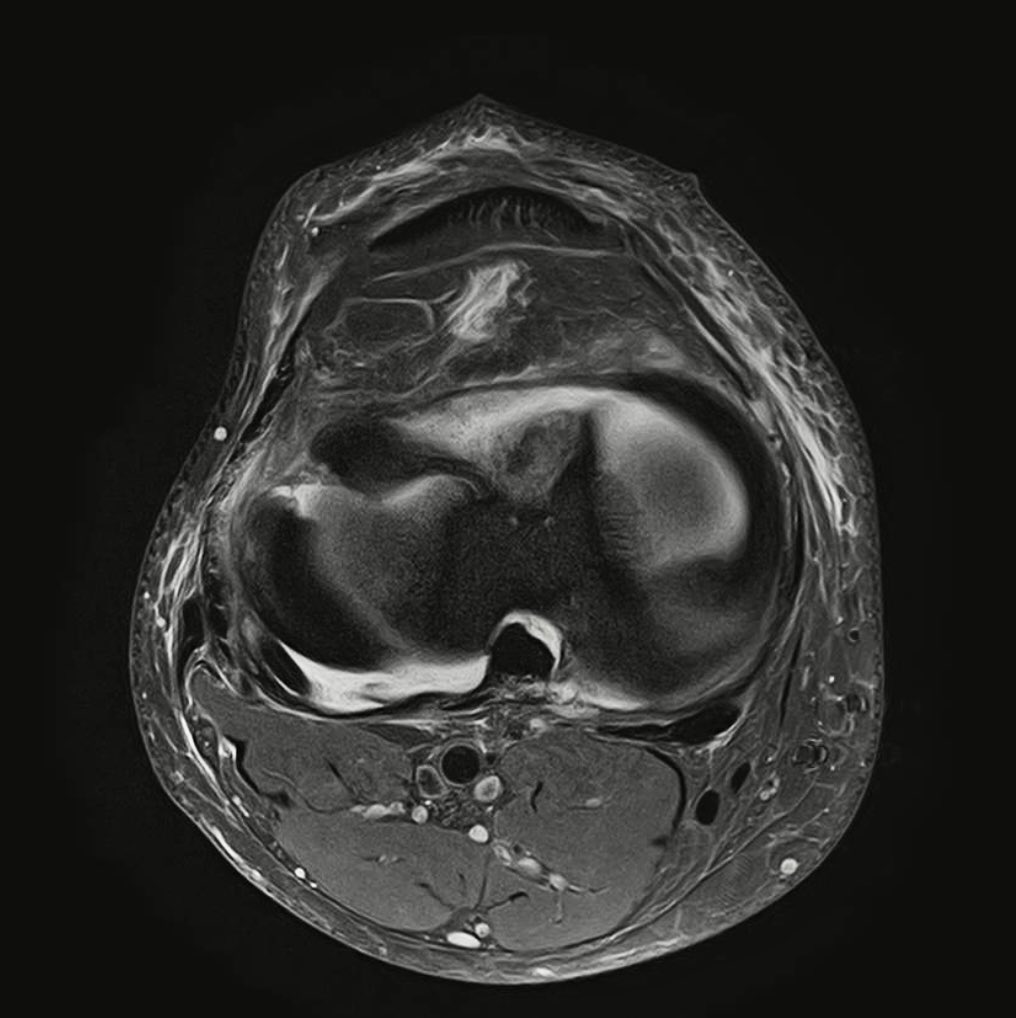

54yo male, professional jiu-jitsu. Complete ACL and this full thickness lateral meniscus radial tear. Would you attempt repair? YES or NOT and justify... ✍️